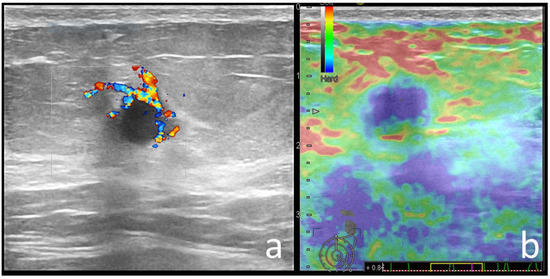

| Echo pattern | 0.000 | ||

| Hypoechoic | 57 (58.2) | 100 (70) | |

| Heterogeneous | 36 (36.7) | 19 (13) | |

| Isoechoic | 5 (5.1) | 26 (17) | |

| Posterior features | 0.000 | ||

| None | 39 (39.8) | 71 (49) | |

| Enhancement | 27 (27.6) | 12 (8.3) | |

| Strain Elastography | 0.029 | ||

| Soft | 40 (40), 9 BGR | 30 (20.6), 1 BGR | |

| Hard | 58 (60) | 115 (79.3) | |

| Margins | C (20/29) | NC (11/15) | NC (11/15) | NC (11/15) | C (5/7) | NC (5/6) | C (3/3) | NC (3/3) |

| Echo pattern | Hypoechoic (19/29) | Hypoechoic (9/15) | Heterogeneous (5/15) | Hypoechoic (11/15) | Hypoechoic (4/7) | Heterogenous (3/3) | - | Hypoechoic (2/3) |

| Posterior features | Enhancement (16/29) | Absent (9/15) | Shadowing (6/15) | Enhancement (6/15)/Combined pattern (5/15) | No posterior (4/7) | - | Enhancement (2/3) | - |

| Associated features | Hyperechoic rim (6/29) Soft elastography (11/29) | Calcifications (7/15) Hard elastography (12/15) | Calcifications (7/15) | - | - | Calcifications (3/6) Hyperechoic rim (3/6) | - | Calcifications (2/3) Architectural distortion (2/3) |